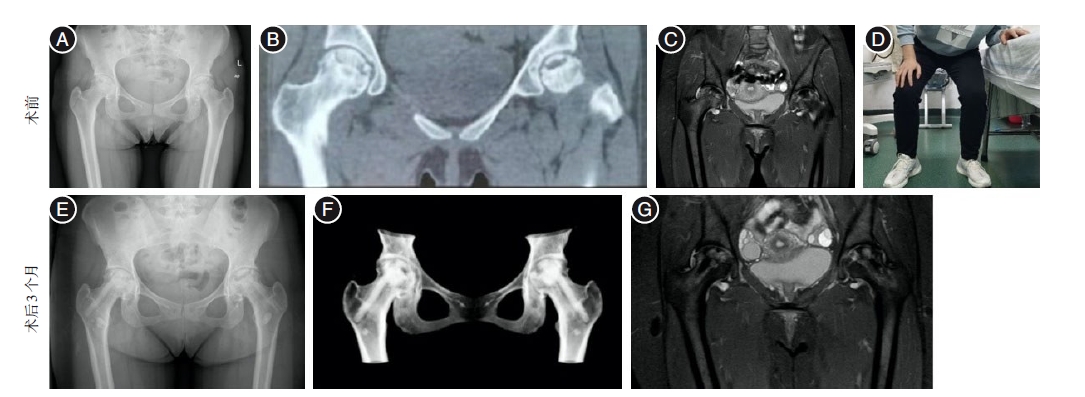

Core decompression combined with BMP activity inducing rod implantation for early femoral head necrosis

Objective To investigate the effect of core decompression combined with bone-morphogenetic proteins (BMP) activity inducing rod implantation in the treatment of early-stage femoral head necrosis. Methods Retrospective analysis of 116 patients with early-stage femoral head necrosis from June 2018 to June 2022 were divided into core decompression combined with BMP activity inducing rod group (BMP group) and allograft bone group. Sixty cases in the BMP group were treated with core decompression combined with implantation of BMP-activated induced rods, and 56 cases in the allograft group were treated with core decompression combined with bone grafting of the allograft bone by punching and compression.The differences in hip Harris scores and visual analogue scores (VAS) of pain between the two groups at preoperative, 6 months postoperative and 1 year postoperative, and the patient treatment response and femoral head survival rate at 1 year postoperative were compared. Results All patients were followed-up, and the difference between the preoperative VAS score and Harris score of the two groups was not statistically significant (P > 0.05), and the VAS score and Harris score of the two groups were significantly improved at 6 months and 1 year after operation, and the BMP group was better than the allograft bone group, with significant difference(P < 0.05). At 1 year after surgery, the Harris hip score excellence rate of the BMP group was higher than that of the allograft bone group, and the difference was statistically significant (P < 0.05); the femoral head survival rate of the BMP group was higher than that of the allograft bone group, and the difference was statistically significant (P < 0.05). Conclusions Core decompression combined with BMP activity induced rod implantation was effective in the treatment of early femoral head necrosis, which accelerated the induction of new bone formation, improved the quality of new bone, provided biomechanical support for the femoral head, and effectively avoided femoral head collapse. Moreover, it has good biocompatibility and couldbe degraded and absorbed in the body, which is worthy of clinical promotion.